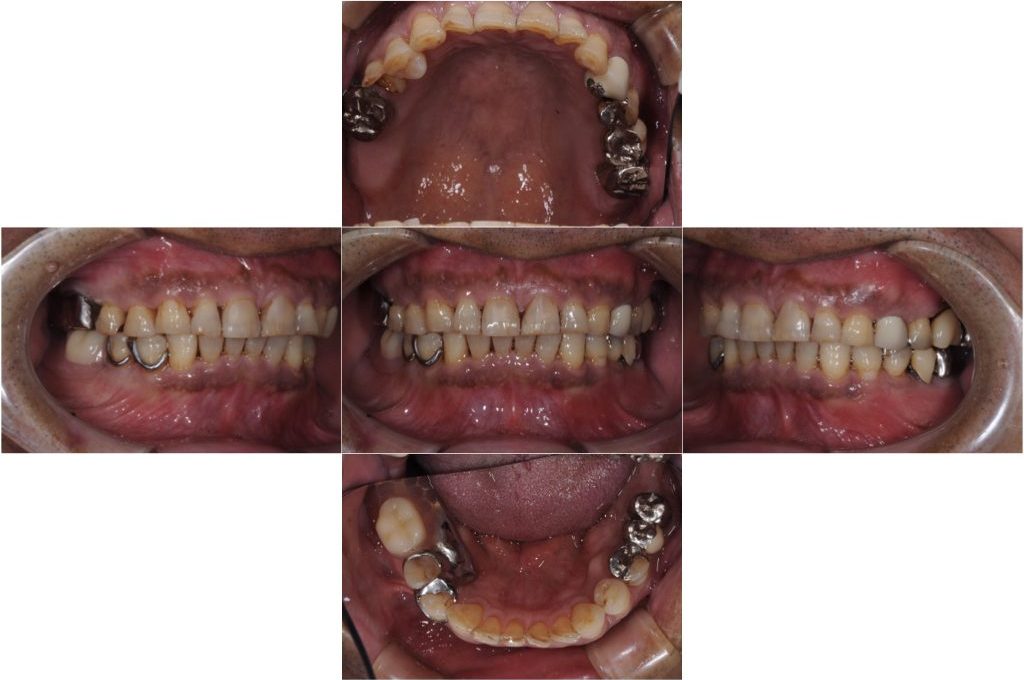

被せ物が外れた(60代)インプラント・セラミック修復

年齢 62歳 性別 男性 初診日 2019年11月 主訴 被せ物が外れた 治療内容 ・インプラント ・セラミック修復 治療期間 8ヶ月 治療費用 250万円 治療経過 主訴は被せ物の脱離であったが、診査の結果、現状抜歯を余儀なくされる歯も見受けられた。 患者様は現在…